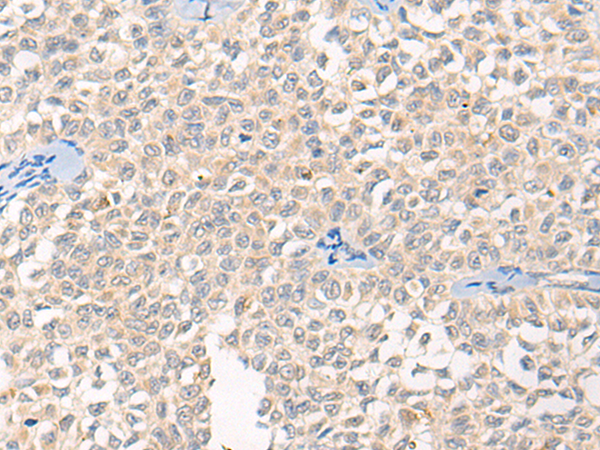

分类: 科研抗体货号: P02471别名: OSM; C7orf22; PP10187应用: IHC反应种属: Human